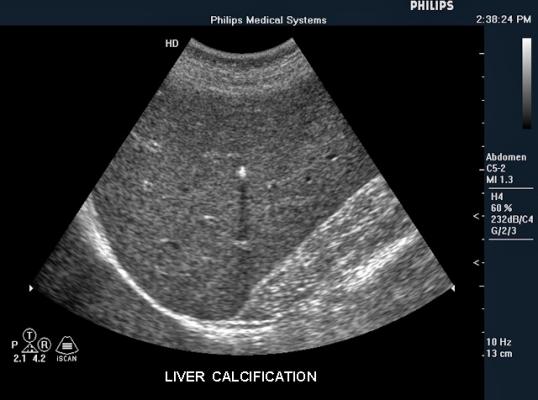

Liver Calcification Treatment

Liver Calcification Treatment Images